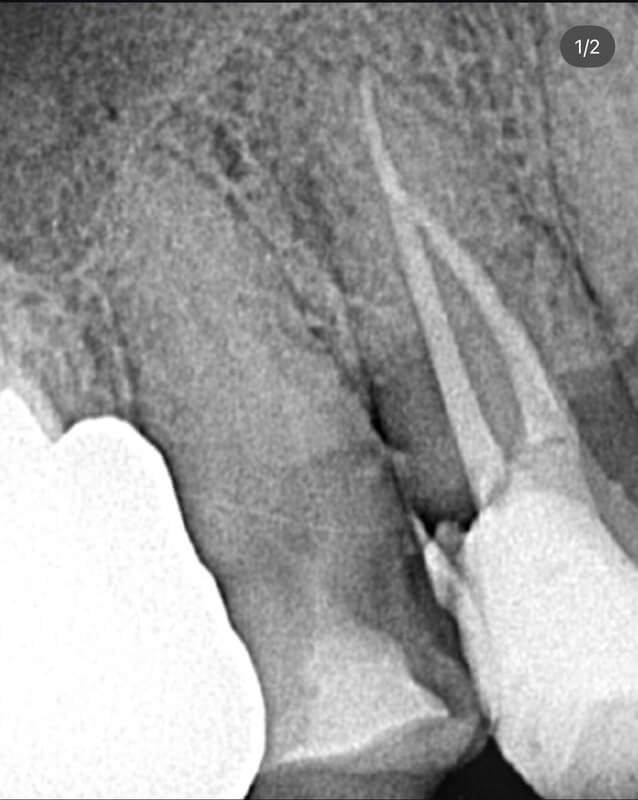

Endodonția este o ramură esențială a stomatologiei, axată pe diagnosticarea, prevenirea și tratamentul afecțiunilor pulpei dentare și a țesuturilor periapicale. Această specialitate joacă un rol crucial în salvarea dinților naturali, evitând extracțiile și menținând sănătatea orală pe termen lung. Prin tehnici avansate și echipamente de ultimă generație, endodonția asigură tratamente precise și eficiente, contribuind la redarea sănătății și funcționalității dinților într-un mod durabil și predictibil.

Utilizarea tehnicilor moderne asigură un tratament rapid, precis și confortabil pentru pacient.